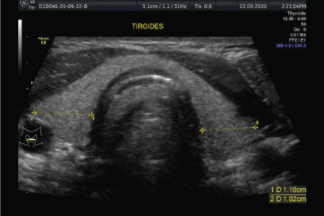

Una biopsia con aguja fina de un nódulo tiroideo es un procedimiento sencillo y seguro. Generalmente la biopsia se hace guiada por ultrasonido para asegurar la colocación precisa de la aguja en el nódulo tiroideo. El procedimiento es menos invasivo que la biopsia quirúrgica, deja poco o nada de cicatriz, y no involucra la exposición a la radiación ionizante.

Primero, se limpia con un antiséptico el cuello. Es posible que se le aplique anestesia local o tópica.

Para la biopsia, se usa una aguja muy fina para aspirar células del nódulo tiroideo. La aguja es más delgada que la que se usa para obtener la mayoría de muestras de sangre.

Se insertará la aguja en el nódulo tiroideo a través de la piel. Luego de obtener la muestra, la cual toma algunos segundos, la aguja se retira.

Nuevas agujas son usadas para obtener nuevas muestras. Se obtendrán varias muestras de células, insertando la aguja en diferentes partes del nódulo, usualmente entre 2 a 6 veces.

Esto aumenta la posibilidad de encontrar células cancerosas en caso de que estén presentes. Si hay líquido dentro del nódulo, puede usarse una jeringa para drenarlo.